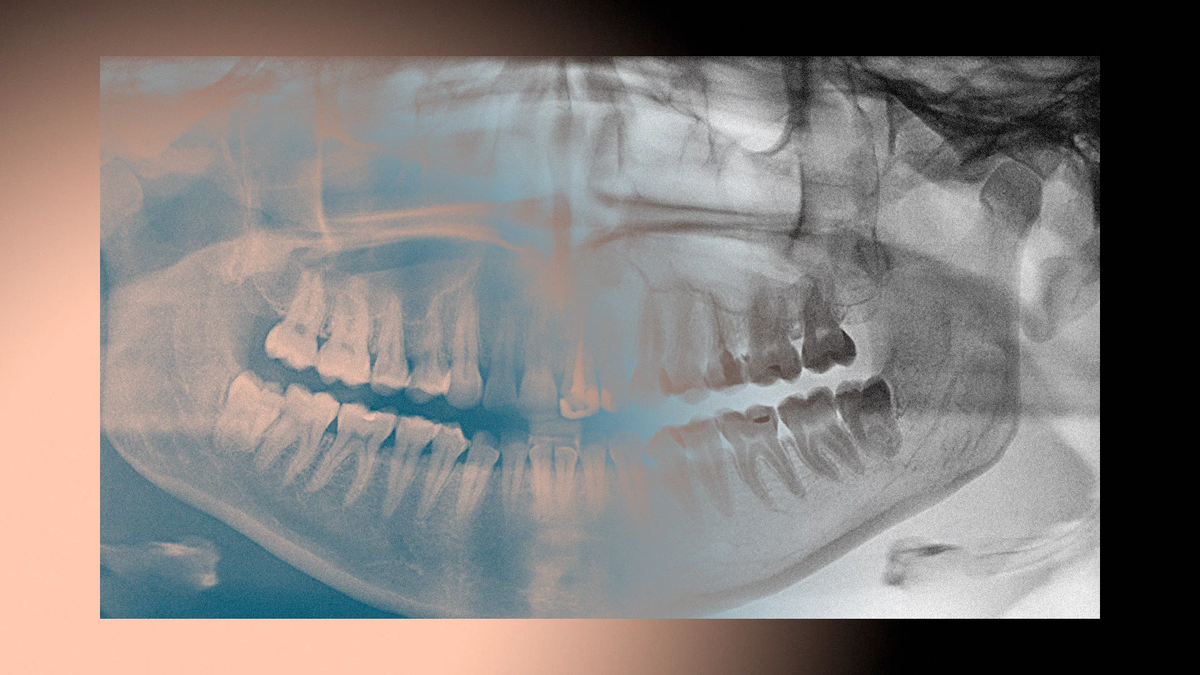

Зубы — казалось бы, просто какие-то эмалированные штуки во рту, ничего сложного. Но почему-то лечим мы их до сих пор очень долго (и дорого), а потеряв, ничего лучше протеза не получаем. Почему мы до сих пор не научились их менять, как грызуны или акулы? Рассказываем, с чем связаны наши зубные проблемы и что нужно сделать, чтобы вырастить новый зуб.

Казалось бы, что может быть проще, чем сделать новый зуб. Его устройство поди проще какого-нибудь кишечника или фаланги пальца. Даже врачи порой шутят, что стоматология — это недомедицина. И тем не менее вырастить хотя бы один из тридцати двух ценных компонентов ротовой полости человека не получается. Заставить их в должной степени обновляться тоже непросто.

В то же время довольно близкие родственники приматов (а значит, и человека) грызуны отращивают новые зубные поверхности всю жизнь и поэтому не боятся кариеса и травм. Резцы у них сразу получаются постоянными, а тем немногим вроде морских свинок, у кого образуется несколько молочных зубов, не приходится ждать противного момента, пока те выпадут: это происходит еще в утробе.

Чем мы не угодили эволюции?

Почему она сделала наши зубы такими недолговечными, что «лечить» их можно только вливанием цемента либо удалением? Есть ли шанс, что когда-нибудь мы сможем отращивать новые зубы вместо того чтобы устанавливать эрзац — протезы?